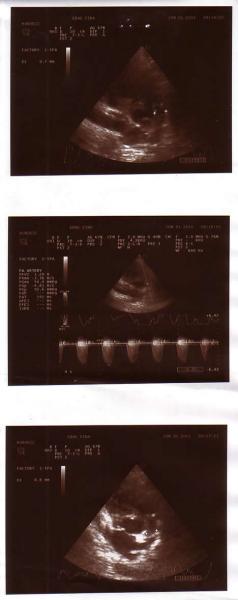

И сейчас мой 4-летний самый младший сынок Муборизи Гозибекпур очень болен: у него врожденный порок сердца. С самого начала нас убеждали, что это израстется, пройдет к трем годам, но оказалось он не числе тех счастливчиков, которых излечивает время. Ребенку срочно нужна операция.